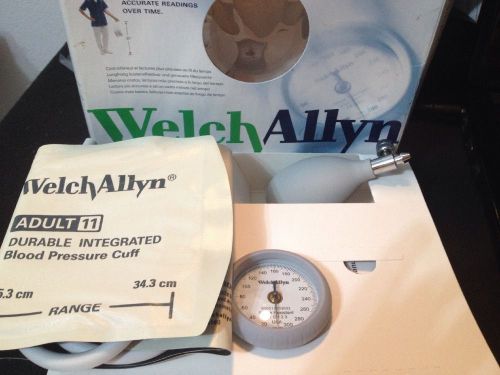

Welch Allyn Durashock Sphygmomanometer Blood Pressure Cuff Adult DS45-11